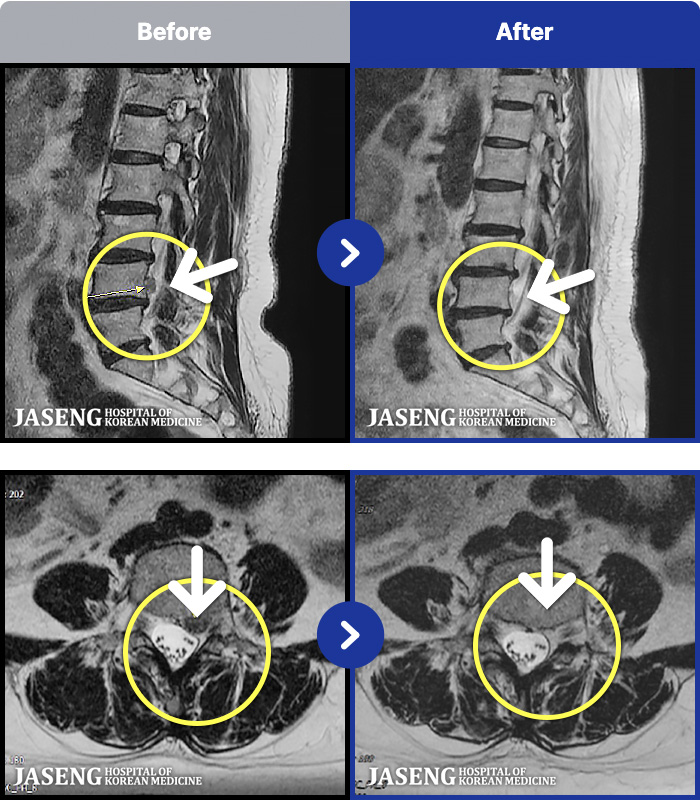

MRI ġ

56 MRI ũ ʸ Ȯϼ.

㸮 ϻ .

[Ȼ] 23.03.13~24.05.08

ȯںп Ǹ ǿ ԿǾ, ο ġ ۿ Ƿ ġḦ Ͻñ ٶϴ.